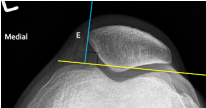

Q what is the name of this measurement? and what is the average + range?

A: Patellar Position

assesses the position of the patella using a ratio of patellar length (PL) to patellar tendon length (PT). The ratio is normally 1:1, with a variation of up to 20%.

A: Sulcus Angle

assesses the depth of the intercondylar groove. The average is 138°, with a range of 132-144°.

A: Lateral Patellofemoral Joint index

assesses for chondromalacia patellae. The index is normally <1.

A: Lateral Patellofemoral Angle

assesses for patellar subluxation. The angle should normally open laterally. No average or range is specified.

A: Lateral Patellar Displacement

assesses for patellar subluxation. The patella should normally lie ≤ 1 mm medial to a perpendicular line from the medial edge of the femoral condyle.